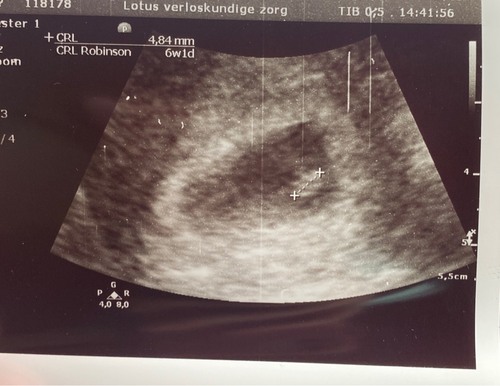

Deze was van 13 oktober, 6w5d. Vanavond termijnecho, ben dan nu 9w3d!